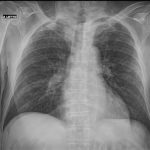

The appropriate position of radiology in COVID-19 diagnosis and treatment—current status and opinion from China

Progress and prospect on imaging diagnosis of COVID-19